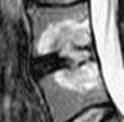

Discopathie L4-L5 MODIC 2